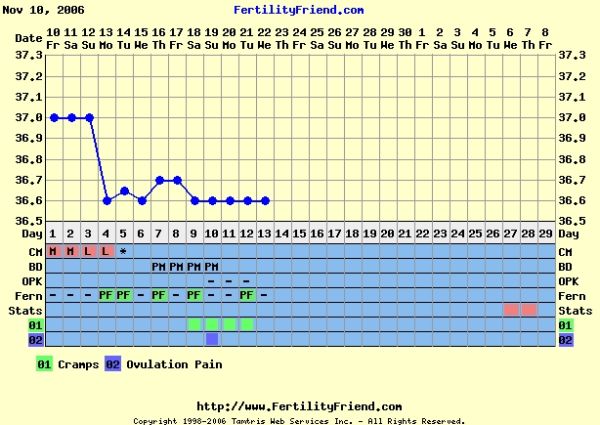

A görbédhez:ha holnap vagy holnap után visszamegy a hőd, akkor nagyon baba gyanús a görbéd

Szirom, szerintem is még korai volt a teszt. Most 13 dpon vagy, varj egy párj napot, a görbéd nagyon szép, ha nem megy holnap lejebb a hőd két nap és tesztelj.

Robcsi, a Te görbéd aztán tényleg kacifántos, de akár mi is lehet, a ferty-n is vannak különleges görbék amiből végül baba lett.